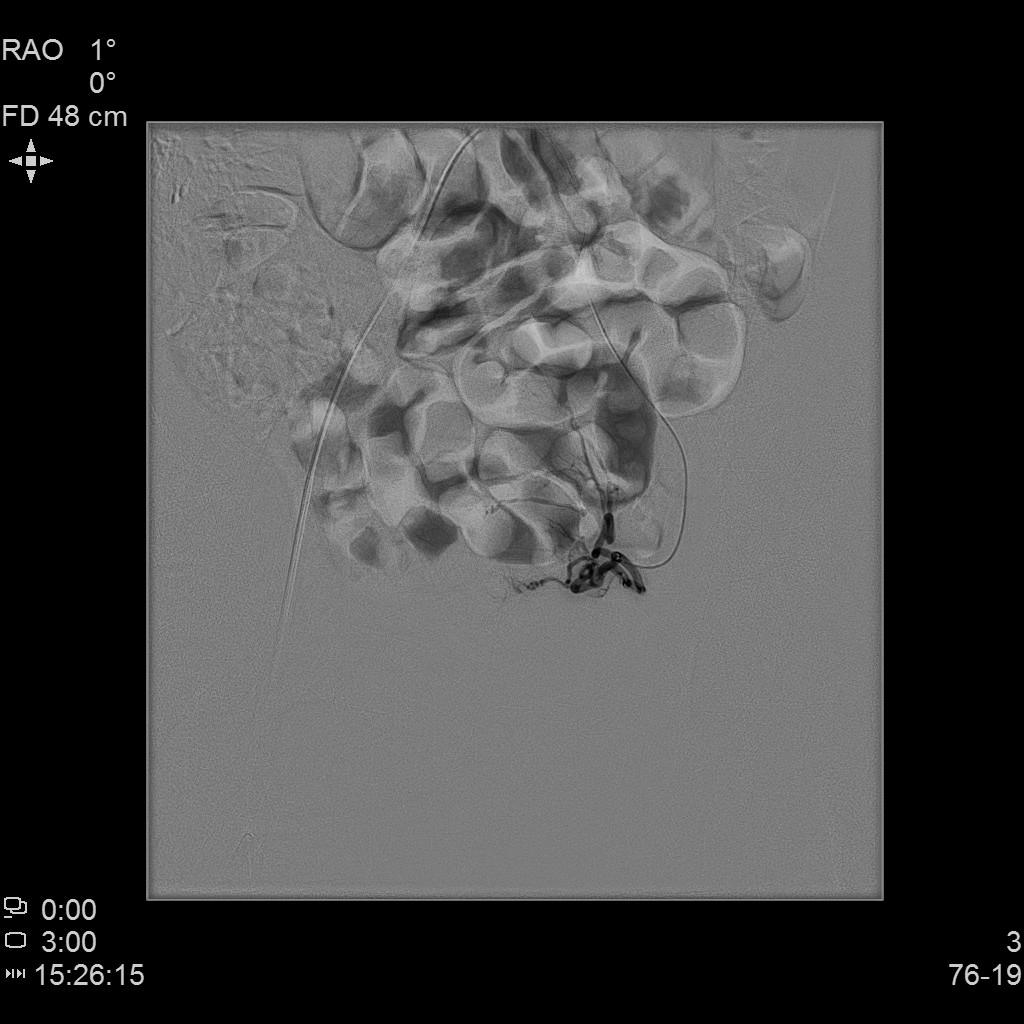

例4

中年女性,痛经10余年,近3个月明显加重。痛经达重度疼痛,严重影响生活质量。磁共振检查显示子宫前壁囊性病灶。临床诊断为囊性子宫腺肌症。

- 经左侧桡动脉穿刺置管,行腹主动脉造影显示双侧子宫动脉增粗、迂曲。

- 超选择插管右侧子宫动脉病灶供血动脉造影+栓塞治疗。

- 超选择插管左侧子宫动脉病灶供血动脉造影+栓塞治疗。

- 术后桡动脉压迫止血6小时,患者术后无需长时间卧床、下肢制动,舒适度明显提高,促进术后快速康复。